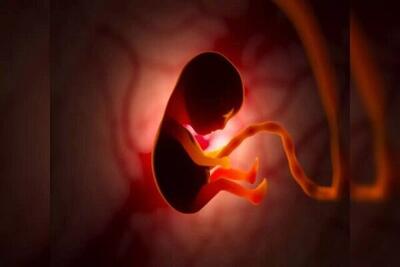

رشد جنین

تشخیص بارداری پوچ یکی از موضوعات مهم در دوران اوایل بارداری است که میتواند برای بسیاری از زنان چالشبرانگیز باشد. این وضعیت زمانی رخ میدهد که کیسه بارداری تشکیل میشود، اما جنین رشد نمیکند و معمولاً در هفتههای ابتدایی بارداری قابل شناسایی است.

جنین در دوران بارداری درون کیسهای به نام کیسه آمنیوتیک رشد میکند. این کیسه پر از مایعی شفاف به نام مایع آمنیوتیک است که از جنین محافظت میکند.

جنین در دوران بارداری درون کیسهای به نام کیسه آمنیوتیک رشد میکند. این کیسه پر از مایعی شفاف به نام مایع آمنیوتیک است که از جنین محافظت میکند.

دانشمندان برای اولین بار توانستهاند «نوتوکورد» را پرورش دهند؛ بافتی که بهمثابه «سیستم هدایتگر» برای جنین در حال رشد عمل و به تشکیل ستون فقرات و سیستم عصبی کمک میکند.

جنین داخل رحم؛ تواناییها و حرکات شگفتانگیز آن+فیلم - سبک ایده آل

جنین داخل رحم تواناییهای شگفتانگیزی دارد؛ از حرکت کردن تا واکنش به صداها و نورها، که رشد آن را در رحم به نمایش میگذارد.